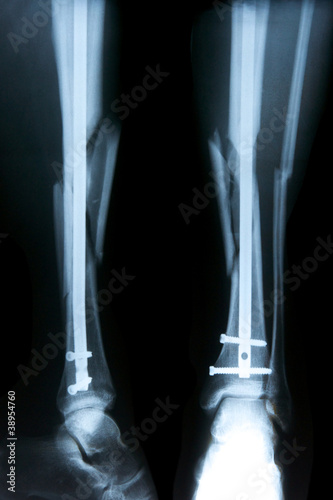

Der Kontakt zum Schienbein erfolgt über eine knorpelige Gelenkfläche, die Facies articularis capitis fibulae, die mit der Facies articularis fibularis tibiae am Condylus . Der Bewegungsapparat des Erwachsenen besteht aus passiven und aktiven Teilen.Überblick über Knochenbrüche. In seltenen Fällen kann es zur .Die andere Möglichkeit, dass ein Wadenbeinbruch (erst) unbemerkt bleibt, ist der Ermüdungsbruch, der auch Stressbruch oder Stressfraktur genannt wird.Ärztinnen und Ärzte sprechen dann von einer Sprunggelenkfraktur. Ermüdungsbrüche können zum Beispiel durch eine längere Wanderung oder beim Joggen auftreten.at-Inhalte werden von medizinischen Fachjournalisten überprüft. Diese Bilder wurde durch Dr. Häufig kommt es beim Sport zu Verletzungen, auch Brüche sind keine Seltenheit. Platten, Schrauben und ein langer Nagel halten zusammen, was zusammengehört.Eine Schienbeinprellung entsteht durch ein stumpfes Trauma (Gewalteinwirkung) auf den Knochen. Bis der Knochen wieder ausgeheilt ist, dauert es im Schnitt etwa fünf bis sechs Wochen. , MD, University of California, San Francisco. Durchschnitt: .Sprunggelenkbruch: Was hilft, wieder auf die Beine zu kommen? Nach der Operation eines Sprunggelenkbruchs kann es kurzfristig Vorteile haben, eine abnehmbare Bandage oder Schiene zu tragen und bereits nach einigen Tagen vorsichtig mit Bewegungsübungen oder Physiotherapie zu beginnen.

Schien- und Wadenbeinbruch